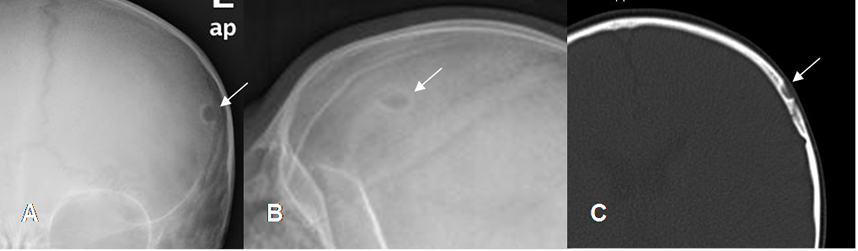

Fig 131. Granuloma Eosinófilo.

A: Rx AP, B: Rx lateral y C: TAC axial. Niño con lesión lítica y de bordes escleróticos, a nivel frontal izquierdo, por granuloma eosinófilo.